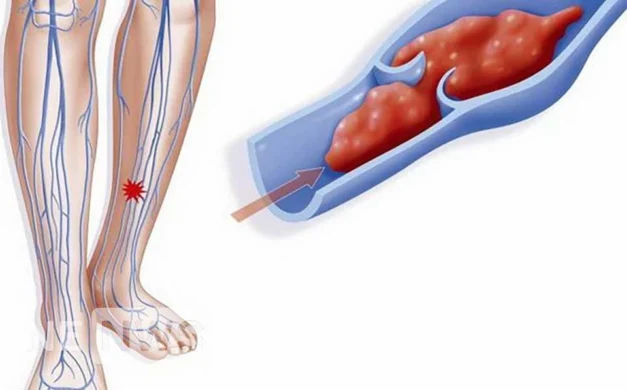

Що таке тромби? Тромб – це згусток крові, що згорнулася. В нормі вони захищають нас при подряпинах та інших ранах: кров згортається, тромб зупиняє кровотечу із пошкодженого капіляра чи вени. А потім, виконавши завдання, протягом кількох годин чи днів ...